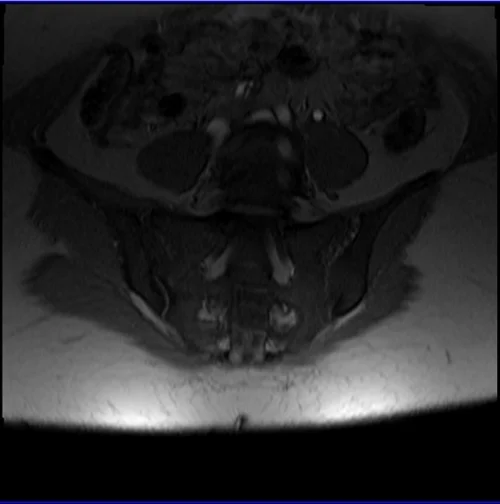

mri sij loc 3 - MRI